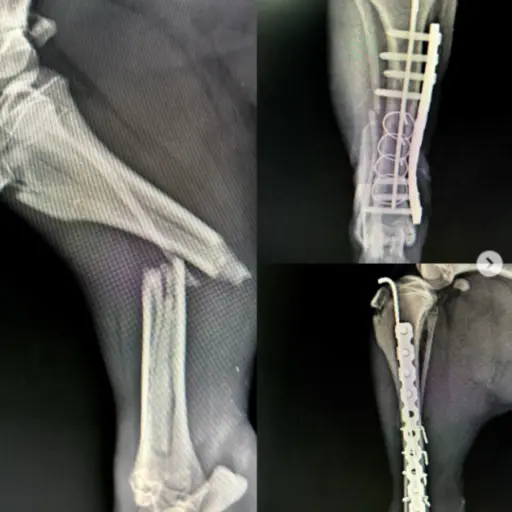

Köpeklerde Diz Kapağı Çıkığı, Çapraz Bağ Kopuğu, Kalça Çıkığı ve Kırık Ameliyatı

Uzmanlık alanları arasında bacak ve kol kırıkları, travma sonucu kalça kırıkları, yüksekten düşme sonucu oluşan travmalar, kranial ve ön çapraz bağ kopmaları, parçalı pelvis kırıkları, eklemden kırıklar, kalça çıkıkları, distal radius ve ulna kırıkları ile doğumsal kalça problemleri gibi birçok ortopedik vaka yer almaktadır.

TTA Çapraz Bağ Kopuğu